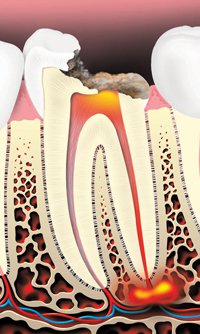

If damaged or infected pulp is not removed, the tissues around the root of the tooth can become infected. Pain and swelling often result. Even if there is no pain, bacteria can damage the bone that holds the tooth in the jaw. Without treatment, the tooth may have to be removed.

Tooth decay can cause an abscess (infection)